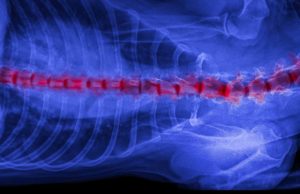

Slipped Disc in Dogs: Causes and Treatment

The most common reason for the appearance of paralysis in dogs is the intervertebral disc herniation or so-called slipped disc in dogs. Like people,...